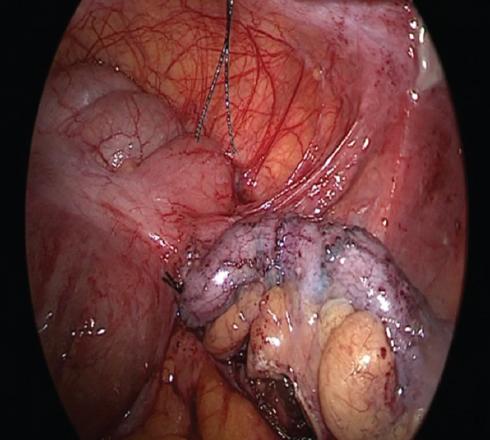

Cirugía realizada: apendicectomía laparoscópica. Abordaje con técnica de Hasson a través de una incisión umbilical de 1 cm, posteriormente se coloca un trocar umbilical de 12 mm y se inicia capnoperitoneo hasta 12 mmHg. Se introduce una lente de 30° y se realiza laparoscopia diagnostica. Se procede a la colocación de trocares de 5 mm, de región suprapúbica y de flanco izquierdo.

Hallazgos: adherencias laxas del epiplón a la pared. Líquido libre purulento de aproximadamente 20 ml. Apéndice vermiforme de 10 cm, hiperémico, edematoso en toda su extensión, con placas fibrinopurulentas. Se realiza apendicectomía y se maneja el muñón con técnica de Halsted. Sin complicaciones, con sangrado mínimo (Figs. 2 and 3).